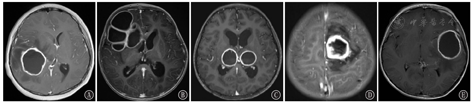

BA MRI典型表现为T1低信号,T2高信号,DWI高信号,ADC低信号,T1动态增强扫描呈环形强化,周围脑组织水肿明显(图1)。47例患儿中,单发型BA 24例(51.1%),多房型BA 9例(19.1%),多发型BA 14例(29.8%)(图2A,图2B,图2C)。根据增强MRI上脓肿壁厚度分类,薄壁组(壁厚<2 mm)28例(59.6%),厚壁组(壁厚≥2 mm)19例(40.4%)(图2D、图2E)。脓肿体积≤4 cm者27例(57.4%),>4 cm者20例(42.6%)。根据脓肿所在位置分类,位于脑深部/功能区(丘脑、基底核、中央区等)15例(31.9%),位于脑浅表部位/非功能区32例(68.1%)。

注:MRI:磁共振成像 MRI:magnetic resonance imaging